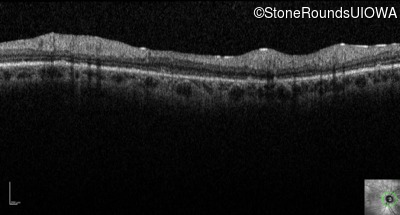

Optical Coherence Tomography - Right - 10/200

Exemplar / OCT Stack